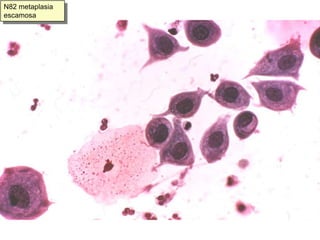

Metaplasia escamosa y zona de transformaciónLa zona de transformación , o unión de epitelios endocervical y exocervical, debe ser muestreada siempre.Por eso debe haber:Células endocervicalesO células de la zona de transformación:Hiperplasia de células de reservaO metaplasia escamosaLa metaplasia escamosa es un proceso patológico que incluimos entre la normalidad celular por su frecuencia en mujeres en edad fértil con ectropion

N81 metaplasia escamosa cervical